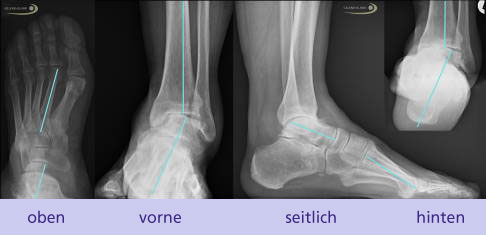

Für die Planung müssen bereits vorliegende Fehlstellungen beurteilt werden. Da die Deformität in allen Raumebenen vorhanden ist und sich die Zugverhältnisse aller Muskeln in Abhängigkeit von der Fußstellung ändern, ist diese Beurteilung besonders wichtig. Weiterhin ist die Untersuchung der statischen, aber auch der dynamischen Funktion beim Gehen sinnvoll.

Die Ganganalyse mit videogestützter Dokumentation kann hier sehr hilfreich sein. Diese Maßnahme erlaubt nicht nur eine Verlaufskontrolle nach einer Operation, sondern kann auch zur Beurteilung der Funktion und Kompensation beim Gehen vor einer Operation herangezogen werden. Auch mögliche Ausgleichsbewegungen am Kniegelenk sind eine Betrachtung wert.

Mögliche komplette und halbe Sehnentransfers

Es gibt eine Vielzahl von Möglichkeiten, je nach Restfunktion der Muskeln die Zugverhältnisse am Fuß durch einen Sehnentransfer zu verändern. Die Zugrichtung der Sehnen hängt von der knöchernen Stellung des Fußes und den noch vorhandenen Bewegungsachsen des Fußes ab. Je nach Lage der Sehnenansätze vor und nach einer solchen Operation gibt es verschiedene Veränderungen, die anhand einer genauen präoperativen Analyse eingeschätzt werden können.